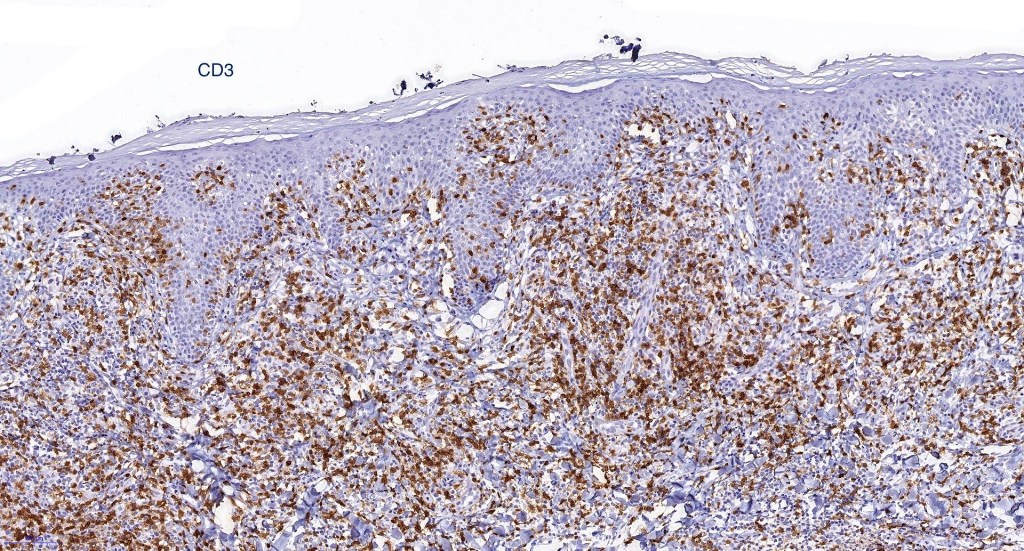

Immunohistochemistry

•Clonal T-cell receptor rearrangement is supportive but not diagnosis of mycosis fungoides as it may be seen in a variety of inflammatory dermatoses

•TCRβ, CD45RO, IL-2R, CLA, CD25, CD2, CD3, CD4, CD5, CD7 +ve

•Much less often CD8+ve

•Variable loss of CD5 (supports the diagnosis) & CD7 (not so helpful as also seen in inflammatory dermatoses)

.TCRγ, TIA, granzyme & EBER -ve